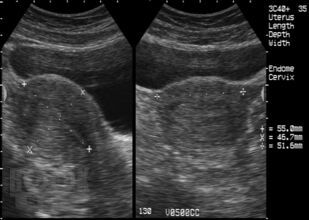

В книге рассмотрены вопросы ультразвуковой диагностики гинекологических заболеваний с общим клиническим синдромом хронических тазовых болей у женщин репродуктивного возраста.

Проанализированы результаты исследований ведущих зарубежных и отечественных специалистов и собственные данные. Определены дифференциально-диагностические возможности эхографии, в том числе цветового картирования, спектральной допплерометрии, при таких заболеваниях, как генитальный эндометриоз, воспалительные процессы внутренних половых органов, включая спаечный процесс, миома матки и т.д. Отражены новые направления диагностики и лечения, приведен протокол ультразвукового исследования органов малого таза.

В книге представлен богатый иллюстративный материал – эхограммы рассматриваемой патологии.